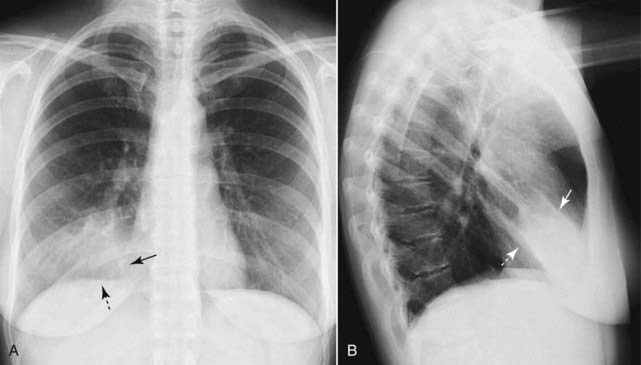

Figure 3-2 Right lower lobe pneumonia.

An area of increased opacification is in the right midlung field (solid black arrow) that has indistinct margins (solid white arrow) characteristic of airspace disease. The minor fissure (dotted black arrow) appears to bisect the disease, locating this pneumonia in the superior segment of the right lower lobe. The right heart border and the right hemidiaphragm are still visible because the disease is not in anatomical contact with either of those structures.